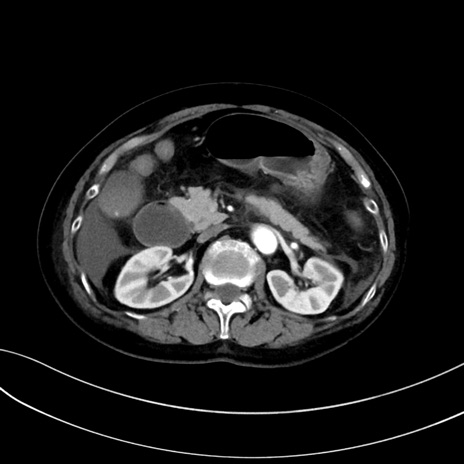

症例13 CT(横断像)1日半後